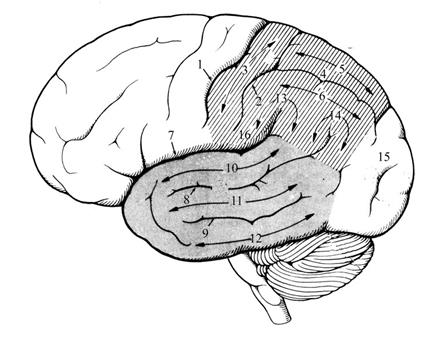

Анатомические снимки верхнелатеральной поверхности головного мозга